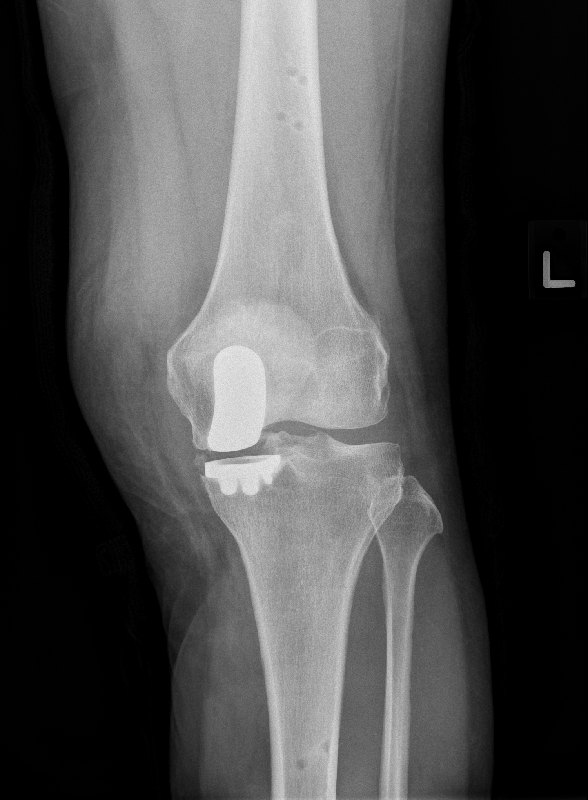

These are the x-rays with the implants in: